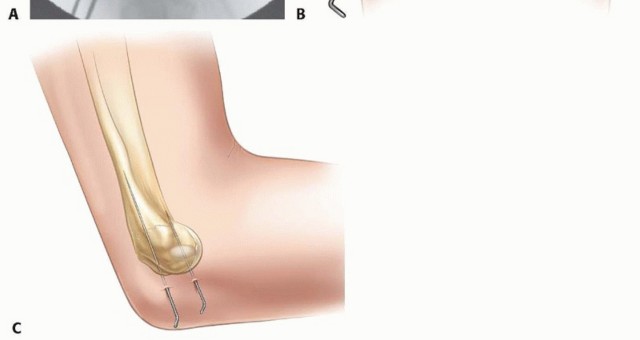

Fixation is typically achieved using two or three smooth K-wires. The biomechanical goal is to provide stable, divergent, or parallel fixation that rigidly resists the rotational and distal pull of the extensor musculature.

- First Wire Placement: The first K-wire is introduced percutaneously or through the incision via the lateral epicondyle, directed proximally and medially across the fracture site. It must cross the fracture perpendicular to the plane of the break and definitively engage the intact medial cortex of the distal humeral metaphysis to ensure adequate bicortical purchase.

- Second Wire Placement: A second K-wire is placed either parallel or divergent to the first wire. A divergent configuration (e.g., one wire aimed slightly anteriorly, the other slightly posteriorly, or one proximal and one distal) provides statistically superior biomechanical resistance to rotation compared to parallel wires.

- Optional Third Wire or Screw: In highly unstable fractures, massive fragments, or in older children, a third K-wire may be added for supplemental stability. Alternatively, a partially threaded cannulated screw (typically 3.5 mm or 4.0 mm) can be utilized in adolescents nearing skeletal maturity. However, screws must not cross an open physis due to the risk of compression-induced physeal arrest.

After pin placement, the tourniquet may be deflated to confirm perfusion. The elbow is taken through a gentle, full range of motion under live fluoroscopy to confirm absolute construct stability and to ensure no pins are inadvertently protruding into the radiocapitellar or ulnohumeral joint spaces, which would cause devastating chondral damage.

The K-wires can be bent and cut outside the skin to facilitate easy removal in the outpatient clinic, or they can be cut short and buried beneath the skin to theoretically reduce the risk of pin tract infection. The choice depends on surgeon preference, institutional protocol, and the reliability of the patient's family regarding cast care and hygiene.